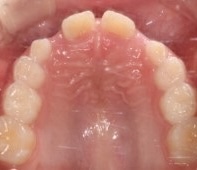

歯列